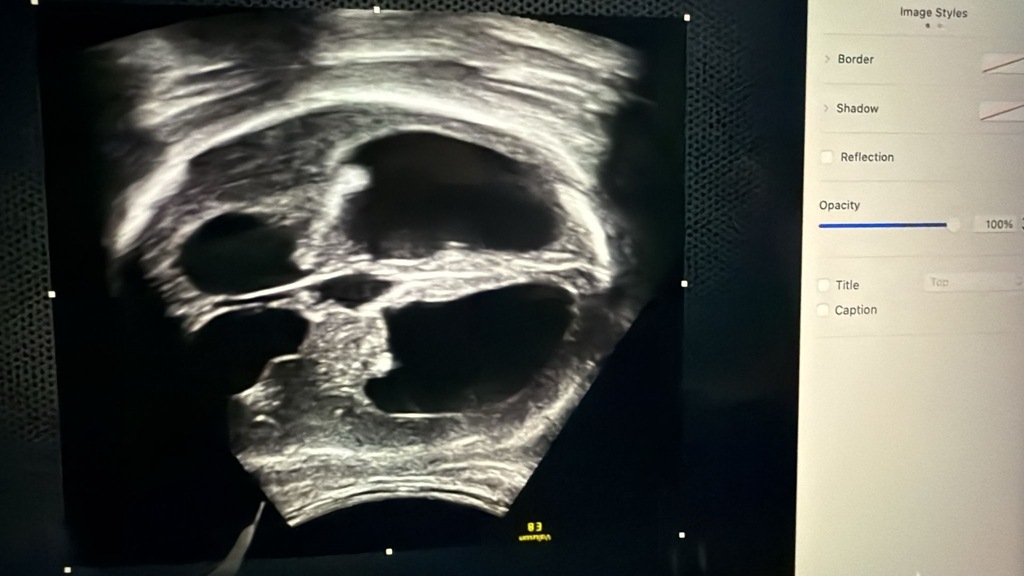

În mod normal, mamele ar trebui urmărite la șase săptămâni, să fie luate în evidență, să stabilim dacă este o sarcină cu risc obstetrical sau este o sarcină normală și de la prima luare în evidență să stabilim împreună cu pacienta o schemă de urmărire care să meargă până la final, până la momentul nașterii. Asta înseamnă, vorbim de o sarcină normală. Este luată in evidență, merge la medicul de familie, facem la 12 săptămâni screening-ul de primul trimestru, care înseamnă o eco-morfologie precoce, în care verificăm o parte din anomalii vizibile și facem screening-ul pentru anomalii cromozomiale, care este foarte important pentru că ecografic nu putem exclude anomaliile cromozomiale. Motiv pentru care este foarte important ca în primul trimestru să se facă acest screening.

După care este urmărirea lunară împreună cu medicul de familie, iar la 20 de săptămâni se face morfologia mare, cum spunem noi, de trimestru 2, unde teoretic putem să vedem 99% din anomalii.

Urmează iar ecografii lunare, analize de sânge lunare pe care le facem împreună cu medicul de familie, iar între 28-32 de săptămâni facem morfologia de trimestru 3, unde iarăși verificăm anomaliile structurale, poate găsim ceva ce am ratat din anumite motive în trimestrul 2 sau anomalii care apar doar în această perioadă, după care, după 32 de săptămîni, deja putem vedea cum a crescut copilul, cum stă copilul și putem să discutăm deja despre modalitate de naștere.